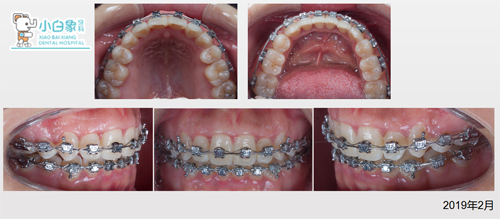

治疗中